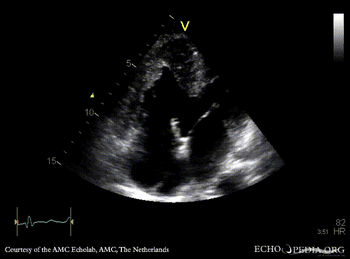

Large VSD, syndrome of Eisenmenger

PLAX: Large VSD